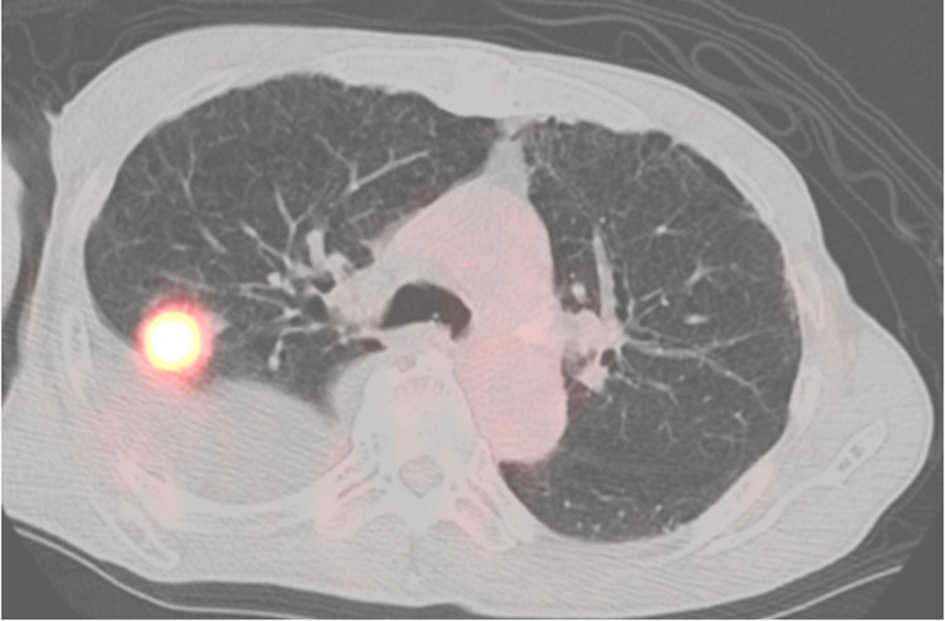

A 77-year-old man was referred to our hospital for right pleural effusion lasting several months with unknown etiology. During follow-up at our hospital, we observed a nodule in the upper lobe of the right lung, showing high 2-deoxy-2-[18F] fluoro-D-glucose (FDG) uptake [Primary tumor standardized uptake value (SUV)max = 12.4] on positron emission tomography-computed tomography (PET-CT) (Figure 1). After excluding malignant pleural effusion via cytological testing, we diagnosed the patient with stage IA3 squamous cell lung carcinoma and performed combined resection of the right upper lobe and part of the middle and lower lobes via video-assisted thoracic surgery. The patient was a heavy smoker (60 packs/year), with a history of radiation-treated laryngeal cancer. He had complications of chronic obstructive pulmonary disease and angina, which were treated with coronary artery stenting.

Figure 1

PET-CT scan showing no FDG uptake in the pleura.